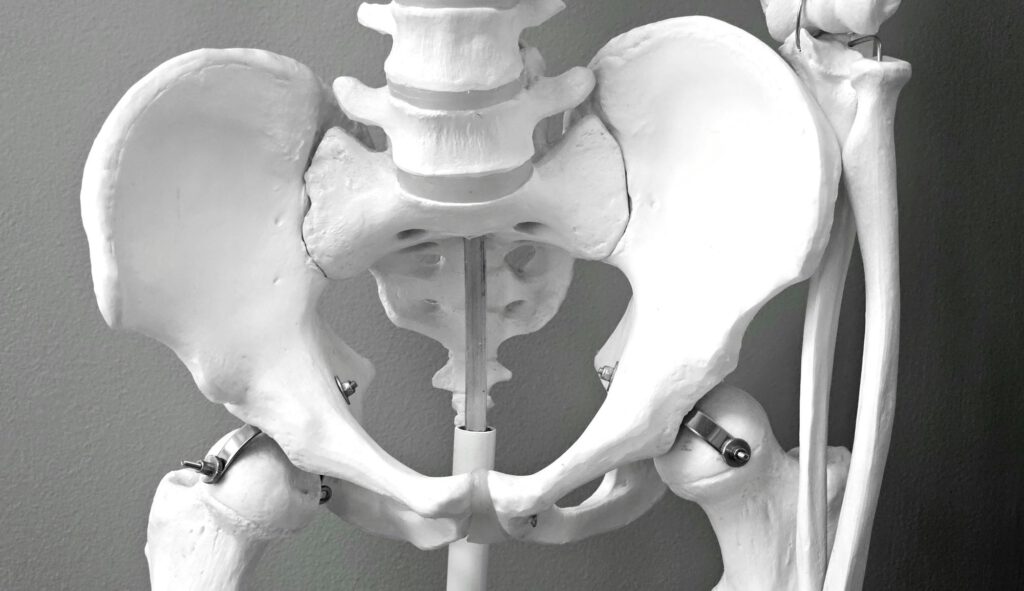

Ob durch Verschleiß, Krankheit oder Unfall: wenn ein Gelenk dauerhaft Schmerzen verursacht und Bewegung stark einschränkt, kann ein Gelenkersatz die Lebensqualität erheblich verbessern. Besonders häufig betroffen sind Knie, Hüfte und Schulter. Der Eingriff gehört heute zum Alltag in der Orthopädie und wird von spezialisierten Orthopäden routiniert durchgeführt. Doch was genau passiert bei solch einer Operation, und woraus besteht eine moderne Prothese?

Die Werkstoffe für künstliche Gelenke müssen besonders hohen Anforderungen genügen: Sie sollen stabil, verschleißfest und gleichzeitig gut verträglich sein. Am häufigsten kommen Metalllegierungen wie Titan oder Kobalt-Chrom zum Einsatz – Materialien, die sich durch hohe Belastbarkeit und eine geringe Allergieanfälligkeit auszeichnen. Für die Gleitflächen, also dort, wo Bewegung stattfindet, wird meist hochvernetztes Polyethylen verwendet, ein Kunststoff mit hoher Abriebfestigkeit. Bei Hüftprothesen findet zudem häufig Keramik Anwendung, da sie wenig Reibung erzeugt und besonders langlebig ist. Welche Materialkombination zum Einsatz kommt, hängt vom betroffenen Gelenk, dem allgemeinen Gesundheitszustand und den individuellen Bedürfnissen der Patient:innen ab.

Knie, Hüfte und Schulter; unsere großen Gelenke haben jeweils ihre eigenen Anforderungen, wenn es um einen Ersatz geht. Eine Hüftprothese etwa ersetzt meist den kompletten Gelenkkopf und die Pfanne. Da es sich um ein Kugelgelenk handelt, lässt sich die Hüfte technisch vergleichsweise gut rekonstruieren. Beim Knie wird es komplexer: Hier müssen Gleit- und Rotationsbewegungen genau abgestimmt werden. Je nach Zustand des Gelenks kommen Teil- oder Totalendoprothesen zum Einsatz. Noch anspruchsvoller ist der Ersatz des Schultergelenks. Es ist extrem beweglich und stark muskelgeführt, sodass auch Sehnenstatus und individuelle Anatomie eine große Rolle spielen.